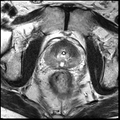

• Testing on 10 clinical datasets was performed using BRAINS+ITK4

• registration was successful in 8 out of 10 cases, based on visual inspection; further investigation is needed for the failed cases and larger scale validation